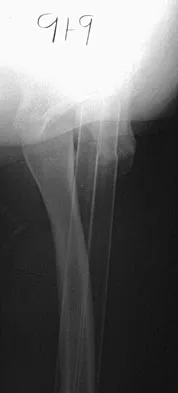

Figure 38 shows the radiograph of a 16-year-old wrestler who injured his elbow when he was thrown to the mat by his opponent. To minimize additional trauma to the medial soft tissues, the elbow should be reduced in